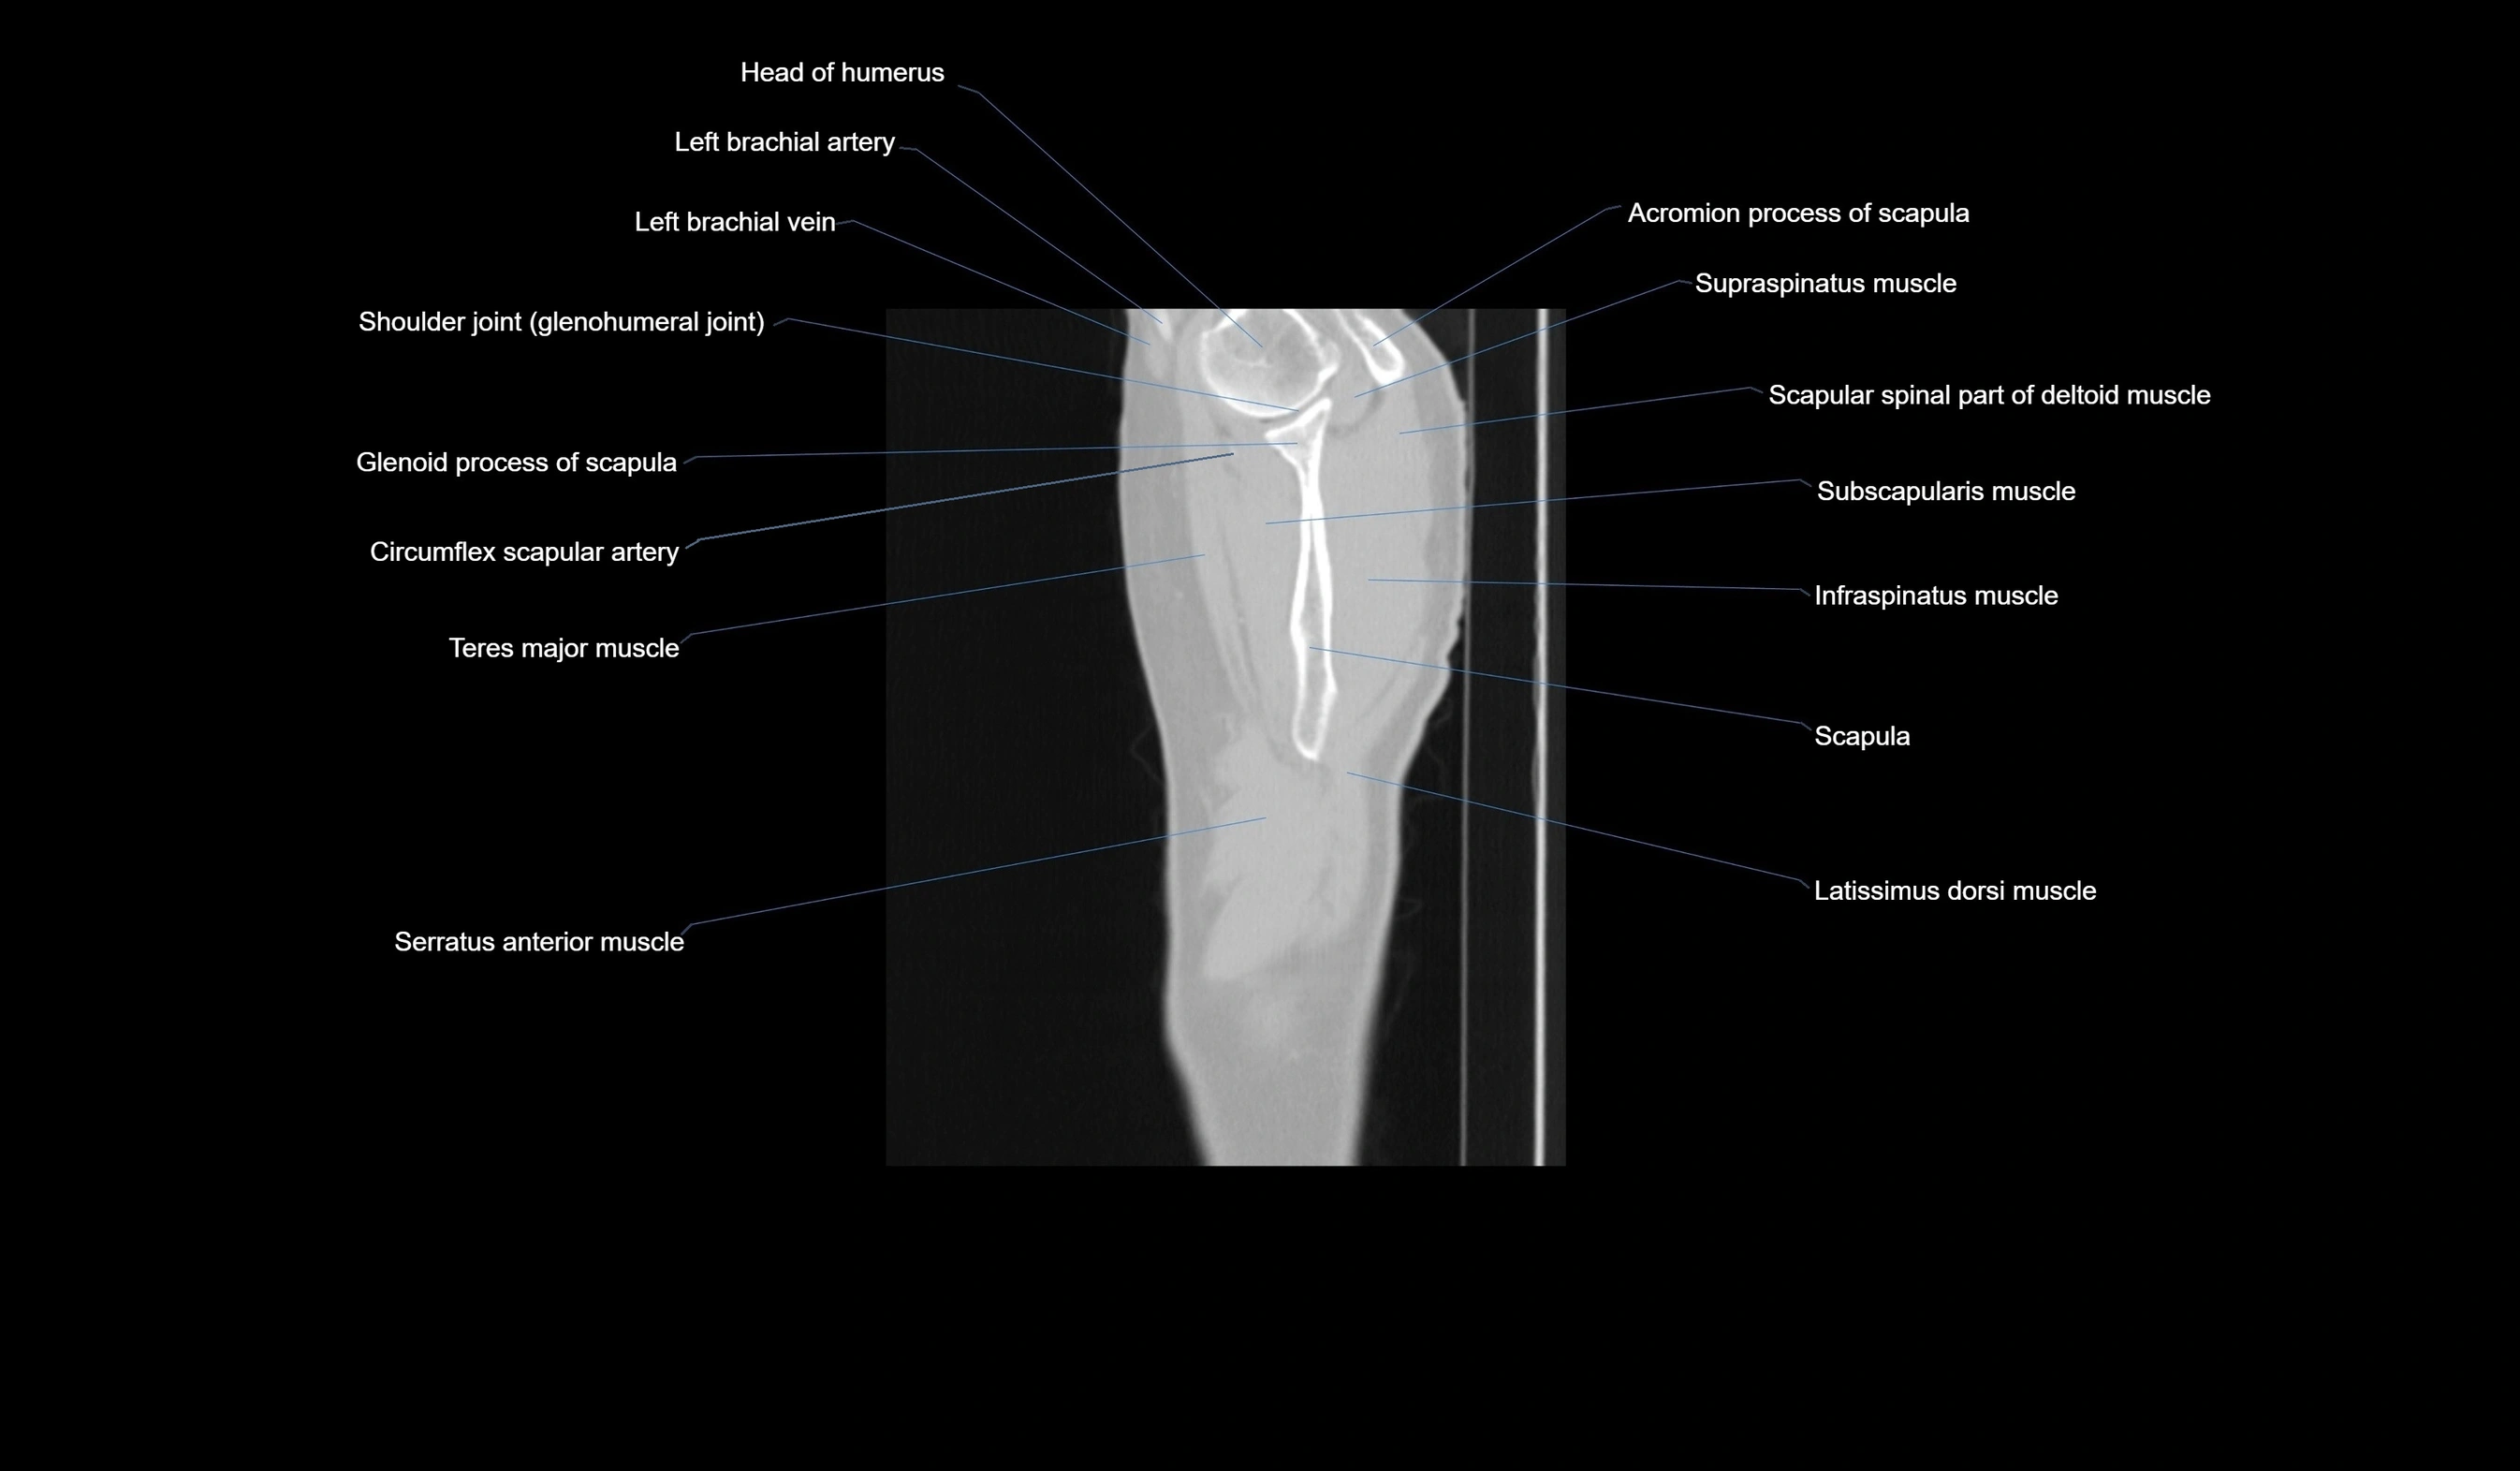

- Shoulder joint (glenohumeral joint)